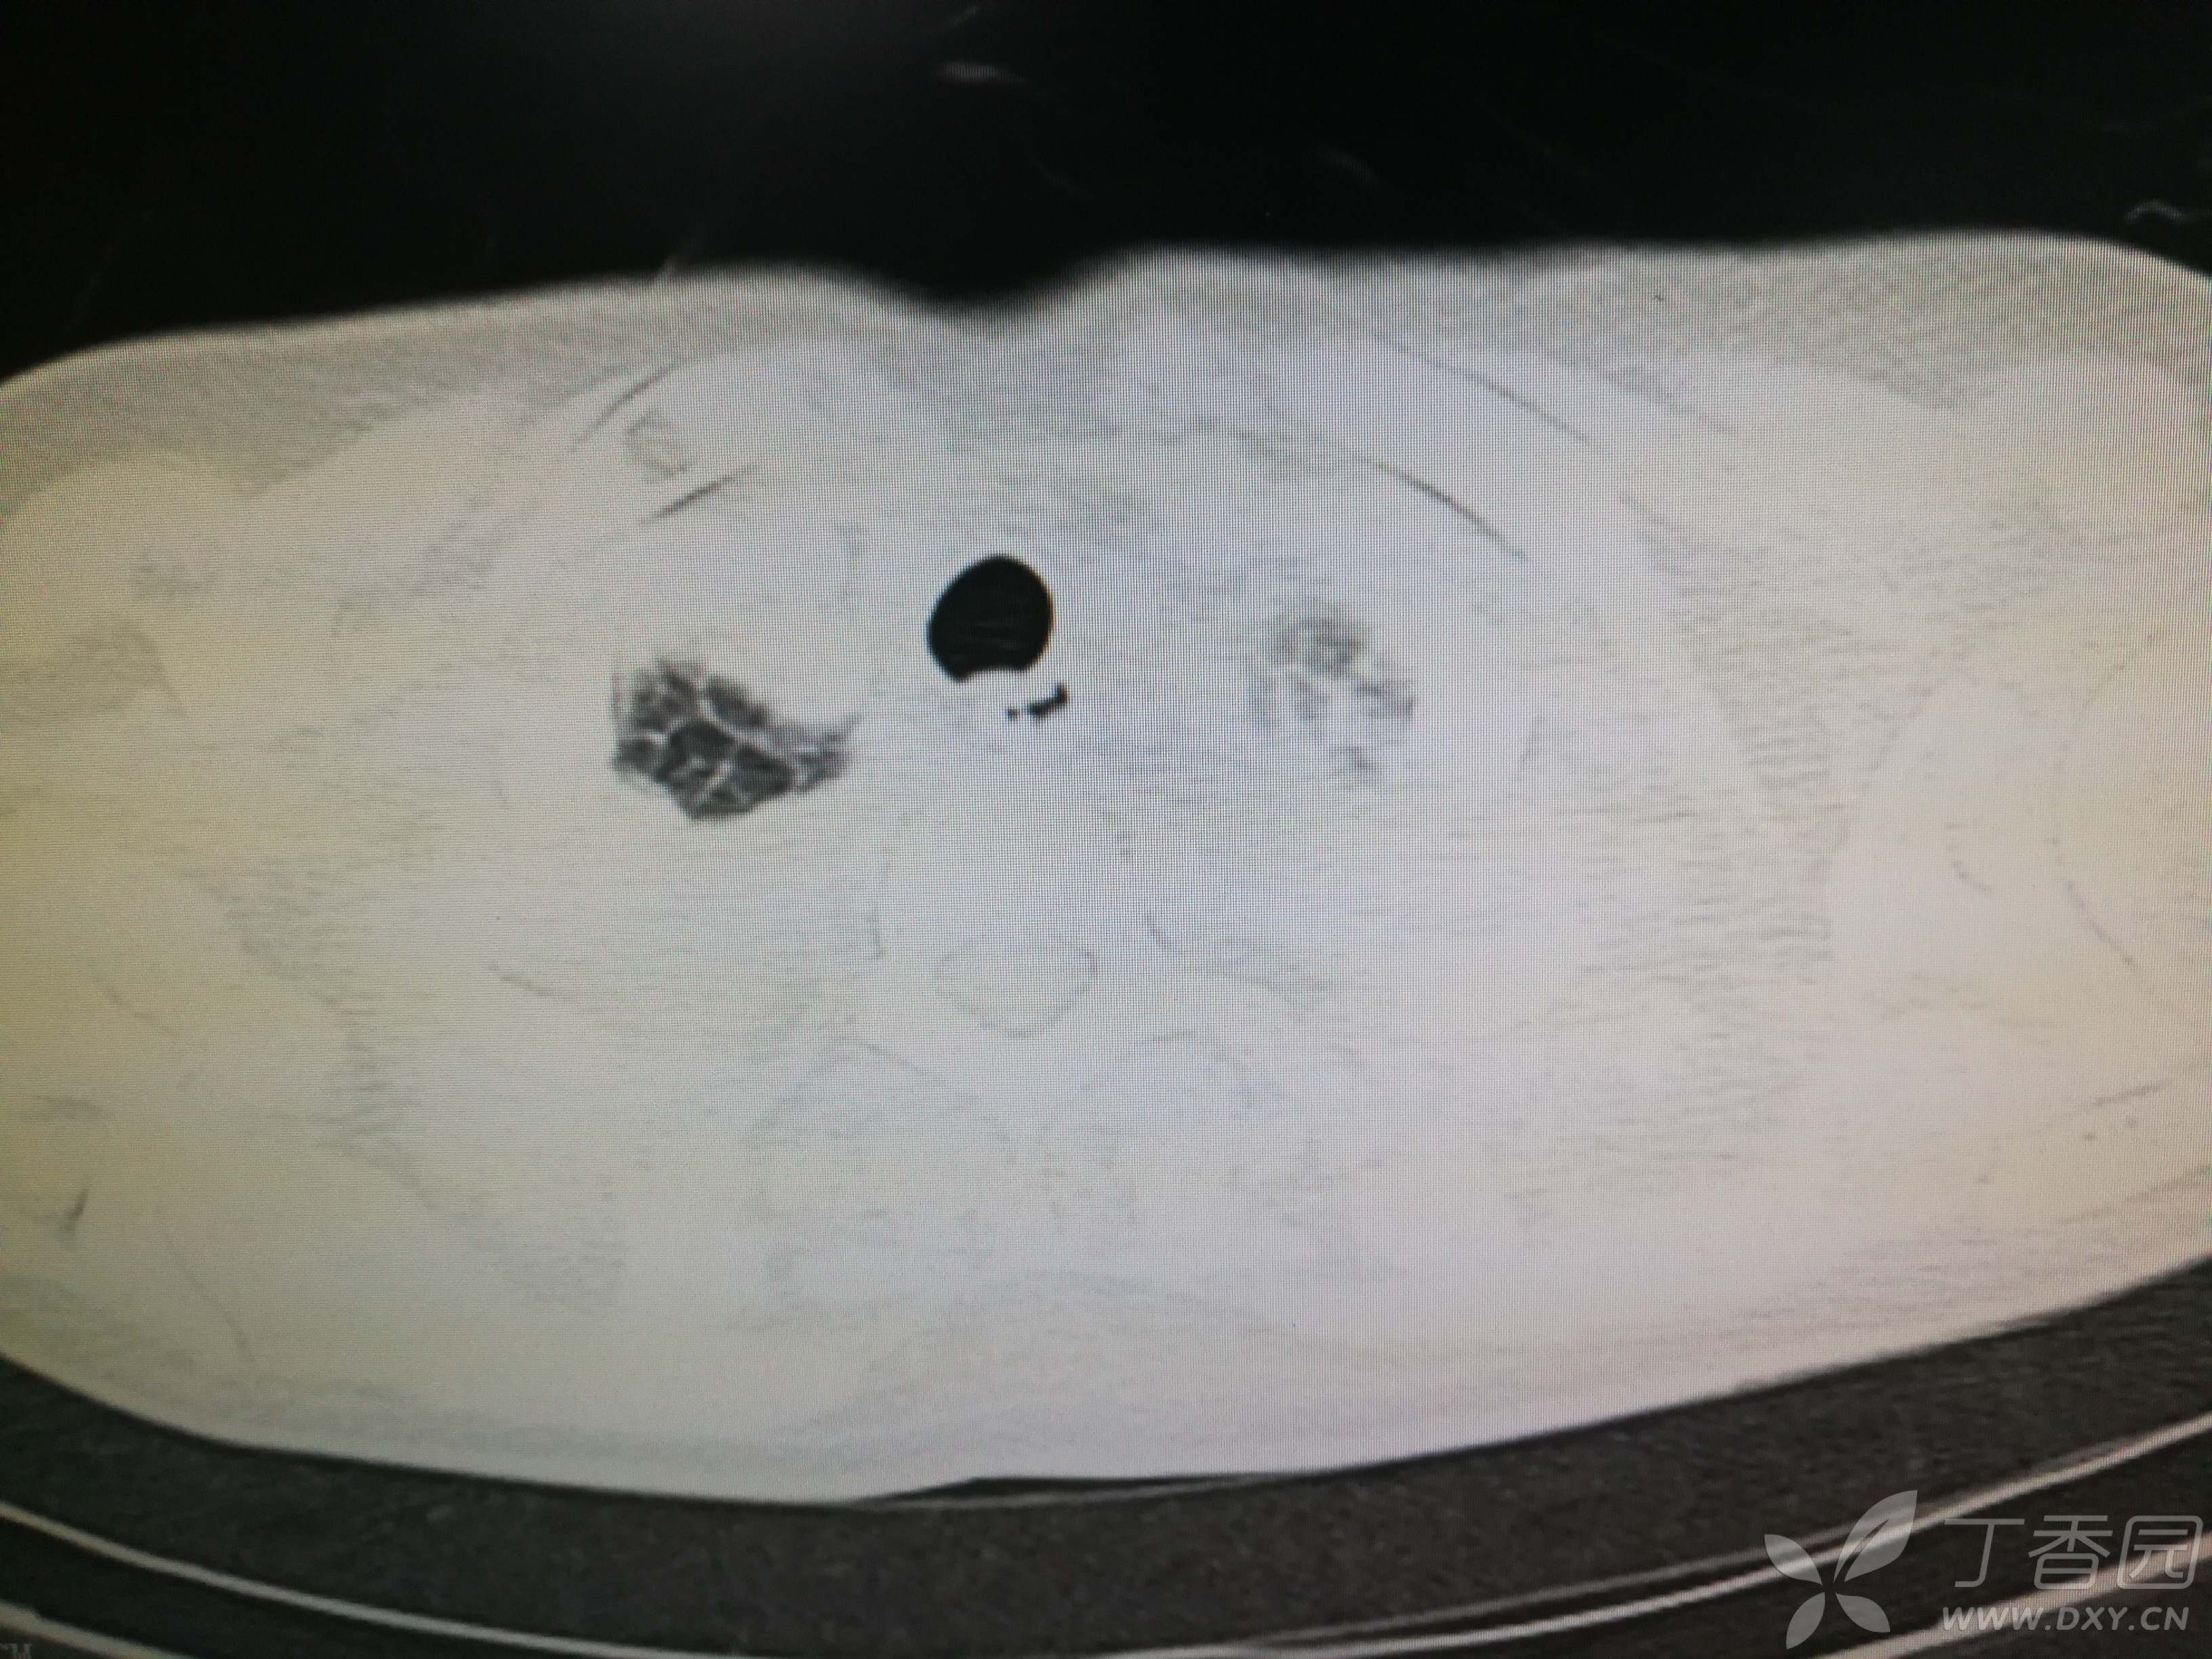

给予低分子肝素钙针抗凝、七叶皂苷钠针消肿及骨牵引固定等等治疗。入院后第四天行“左侧股骨下段骨折切开复位内固定术”(术前查双下肢彩超:双下肢深静脉血流通畅),手术顺利,术后予预防感染、预防血栓形成等治疗。术后患者无明显发热,生命体征平稳。术后第四天复查血常规:白细胞13.4×109/L,血红蛋白84g/L,血小板在正常范围。生化:白蛋白35.7g/L,余无明显异常。当天,患者开始出现轻度胸闷气急,可耐受。术后第五天患者胸闷气急加重,无胸痛,无背痛,无咯血,无意识障碍,无头晕头痛,无恶心呕吐等,急查凝血功能:纤维蛋白原降解产物12mg/L,D二聚体4000ug/L,余无明显异常。查动脉血气分析:pH7.52,氧分压62mmHg,二氧化碳分压30mmHg,碱剩余1.8mmol/L,乳酸1.0mm/L,血红蛋白86g/L。查胸部CT见下(先视频后图片):